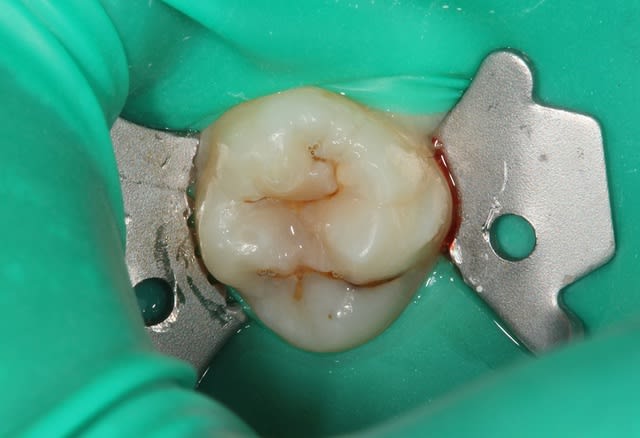

DOULET_I_20111201_1010_xieidx.jpg

Voir le message contenant cette image